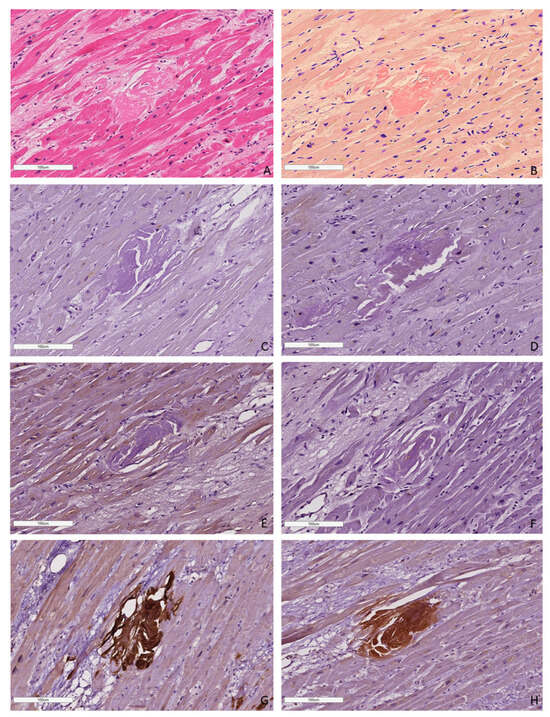

Based on these findings, we can conclude that the AL type of amyloidosis is often characterized by a diffuse pericellular and intravascular deposition of amyloid, while the ATTR type usually demonstrates focal interstitial dense amyloid deposits. AA amyloidosis in most cases is represented by the intravascular deposition of amyloid masses (Figure 5 and Figure 6).

Figure 6. Microscopic images of cardiac tissues in patients with different types of amyloidosis. AL amyloidosis is characterized by diffuse pericellular and intravascular deposition of amyloid displaying apple-green birefringence under polarized light (A,B—AL kappa amyloidosis; C,D—AL lambda amyloidosis (white arrow)). Nodular interstitial amyloid deposits in ATTR amyloidosis with typical apple-green birefringence under polarized light (E,F (white arrow)). AA amyloid deposits within vascular walls, displaying apple-green birefringence under polarized light (G,H (white arrow)). Staining with CR, ×200.